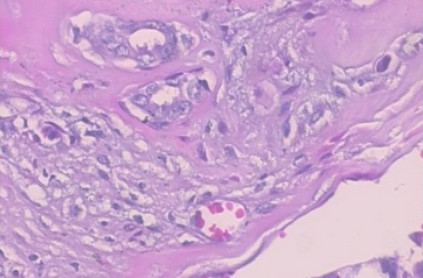

Background: Breast cancer has the highest prevalence in women globally. The classification and diagnosis of breast cancer and its histopathological images have always been a hot spot of clinical concern. In Computer-Aided Diagnosis (CAD), traditional classification models mostly use a single network to extract features, which has significant limitations. On the other hand, many networks are trained and optimized on patient-level datasets, ignoring the application of lower-level data labels. Method: This paper proposes a deep ensemble model based on image-level labels for the binary classification of benign and malignant lesions of breast histopathological images. First, the BreakHis dataset is randomly divided into a training, validation and test set. Then, data augmentation techniques are used to balance the number of benign and malignant samples. Thirdly, considering the performance of transfer learning and the complementarity between each network, VGG-16, Xception, Resnet-50, DenseNet-201 are selected as the base classifiers. Result: In the ensemble network model with accuracy as the weight, the image-level binary classification achieves an accuracy of $98.90\%$. In order to verify the capabilities of our method, the latest Transformer and Multilayer Perception (MLP) models have been experimentally compared on the same dataset. Our model wins with a $5\%-20\%$ advantage, emphasizing the ensemble model's far-reaching significance in classification tasks. Conclusion: This research focuses on improving the model's classification performance with an ensemble algorithm. Transfer learning plays an essential role in small datasets, improving training speed and accuracy. Our model has outperformed many existing approaches in accuracy, providing a method for the field of auxiliary medical diagnosis.